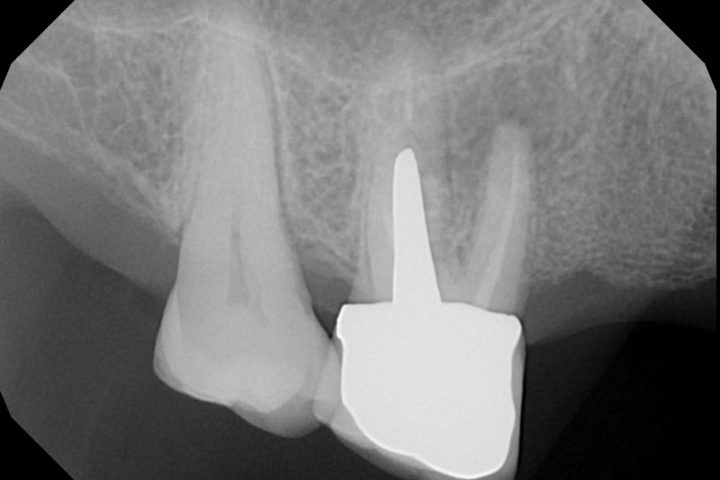

PRIMA

Radiografia – Prima e dopo apicectomia

L’immagine mostra il confronto radiografico tra la situazione iniziale, con evidenza di infezione all’apice radicolare, e il risultato post-operatorio dopo l’intervento di apicectomia: rimozione dell’area infetta e sigillatura della radice completata con successo.